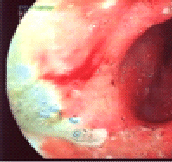

Эта неприметная бактерия является виновником развития у человека хронического антрального гастрита (изменение слизистой оболочки по типу "булыжной мостовой"),

хронического эрозивного гастродуоденита,